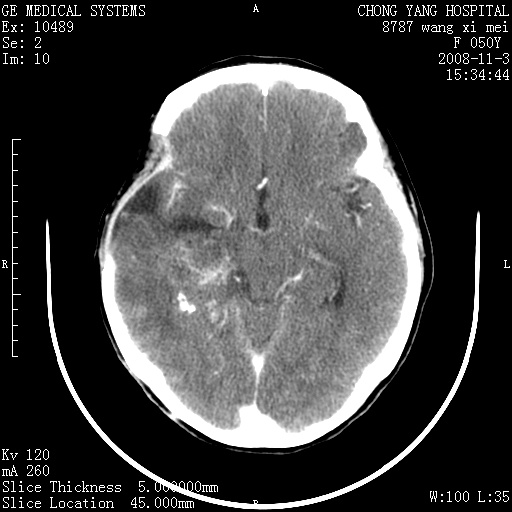

标题: CT16469:女,50岁,胶质瘤术后6年,今平扫加增强,请大家帮 [打印本页]

标题: CT16469:女,50岁,胶质瘤术后6年,今平扫加增强,请大家帮

右侧颞顶部可见低密度实变影,内见不规则钙化灶,边界不清,占位效应明显,侧脑室后角受压移位,符合胶质瘤术后复发改变。

右颞骨局限性缺如,局部脑组织无外隆。右颞叶可见片状脑脊液样低密度影,边缘较清,右侧侧脑室三角区可见一块状等密度影,且伴有强化,余未见明显异常改变。

考虑:右大脑术后改变伴肿瘤复发。

手术后局部片状低密度改变(软化灶),其后方颞叶似等密度病灶,界限不清,内见钙化,有轻度占位效应,但增强后强化之血管走行如常。应不考虑:复发!

考虑右侧颞顶叶胶质瘤术后复发。

应考虑肿瘤复发,右颞顶叶已出现轻度强化肿块.必要时可与原片比较以下.

右侧颞顶部混杂密度影,内有钙化,有占位效应。应该是复发灶。结合术后片更好。